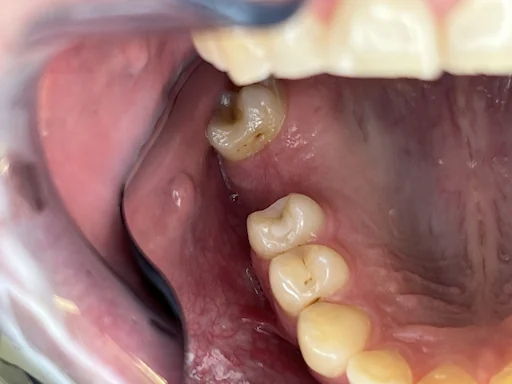

Patientenfall Implantologie: Fehlender Zahn 16 - Ausgangssituation

Schritt 1

In diesem Fall stellte sich der Patient mit einer länger bestehenden Situation Regio 16 vor.